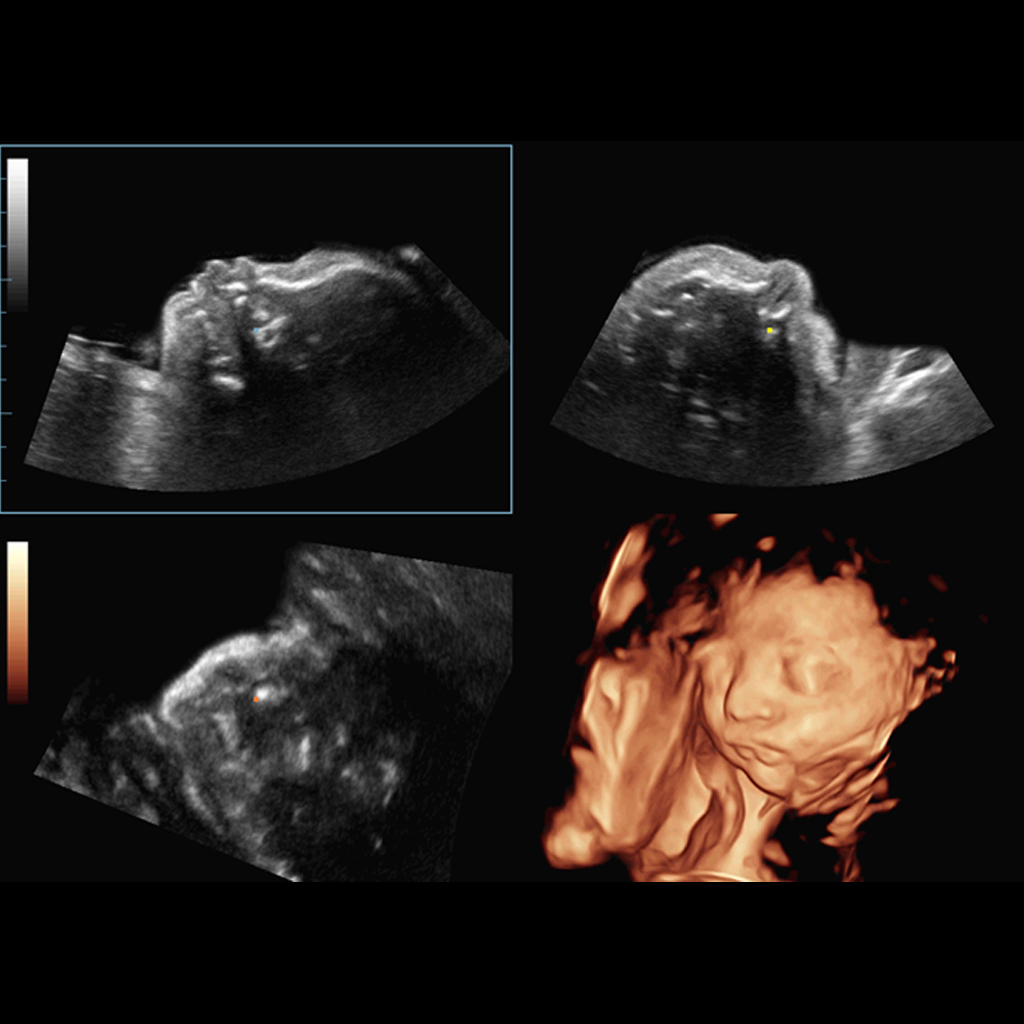

Получаването на оптимален изглед на феталното лице в 3D отнема много време, в някои случаи е невъзможно да се отървем от оклузии като пъпна връв, плацента, матка и крайниците. Само с натискане на един бутон и бебешкото лице, и оклузиите, могат лесно да бъдат разграничени.